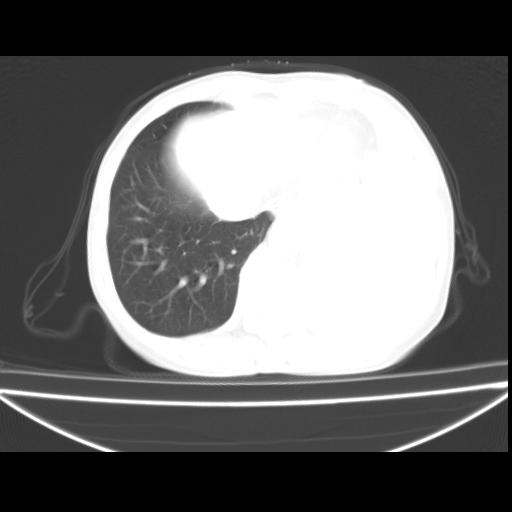

以下是引用随光逐影在2010-3-24 19:15:00的发言:[br]结合病史,考虑双肺及纵隔淋巴结多发转移、左侧胸膜转移并左侧大量胸水,左下肺膨胀不全。

以下是引用zxl51642在2010-3-24 18:49:00的发言:[br]结合乳腺癌术后病史,考虑双肺及纵隔淋巴结多发转移、左侧胸膜转移并左侧大量胸水、左下肺膨胀不全。